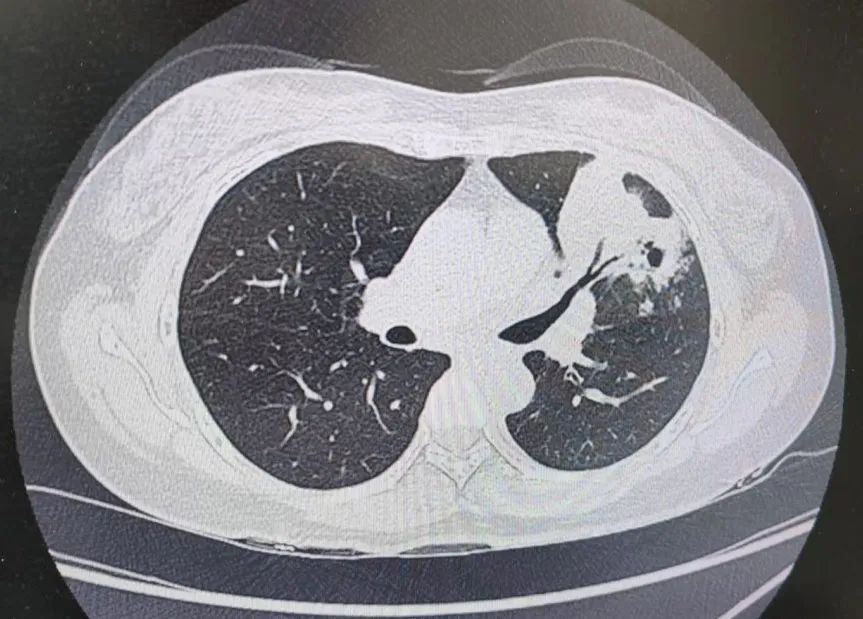

患者肺部CT影像

“一般来说,肺炎经过一周的抗感染治疗,病灶会有所吸收。但陈女士的肺部阴影纹丝不动,这种情况必须提高警惕。”宋刚主任团队立即启动了更深入的“三部精准诊断”程序:

3、CT引导下穿刺活检:病理诊断为左肺上叶腺癌。

肺炎型肺癌,因其影像学表现与普通肺炎极为相似,临床上误诊率极高。然而确诊仅是第一步。宋刚主任当天即召集肿瘤科、病理科、影像科等多学科专家会诊,为陈女士制定个体化治疗方案。